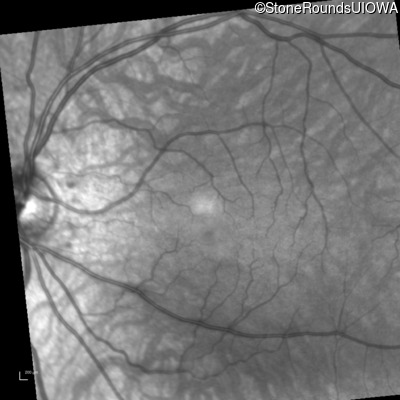

Infrared Fundus Photograph - Left - 20/200 +2

Exemplar